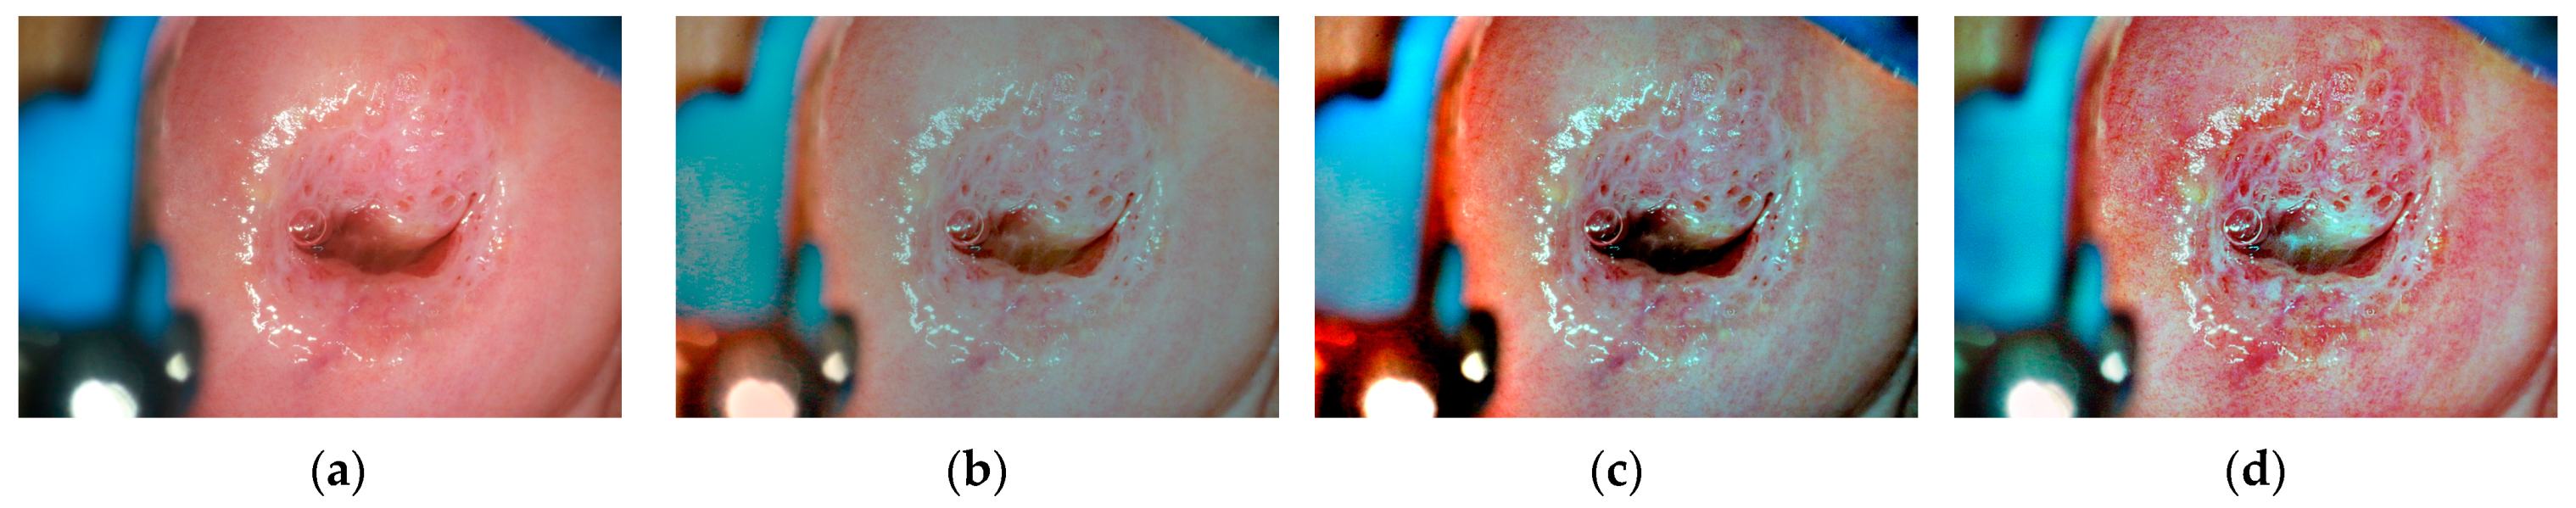

- This paper selectively applies the contrast-limited adaptive histogram equalization (CLAHE) algorithm to the blue and green channels, which contain more detailed information, to improve the contrast between lesion areas and the background without excessive enhancement.

4.3. Subjective and Objective Evaluation